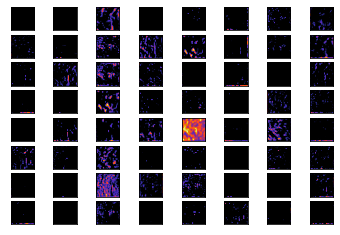

Refer to caption

(a) Colon Loss

(b) Colon Accuracy

(c) Lung Loss

(d) Lung Accuracy

Figure 4: Delineates the accuracy and loss metrics plot over steps. (a), (b) reports the loss and accuracy metrics over all the 100 steps for the colon model. Similarly, loss and accuracy for lung model is described in (c), (d)

To better assess performance metrics, Figure 4 visualizes the plot between epochs vs loss and accuracy. It is quite transparent that there are jitters in all the accuracy and loss graphs due to the dropout layer which helps the neural network generalize. However, there is a slight aberration in the plots of colon, i.e., validation loss increases initially upto 5 epochs then starts to converge. Also, it can be inferred that there are large spikes in both accuracy and loss for the colon model at around 58thsuperscript58𝑡58^{th} and 80thsuperscript80𝑡80^{th} epoch. For both the models it could also be extrapolated that both the models took around 20 epochs to converge.